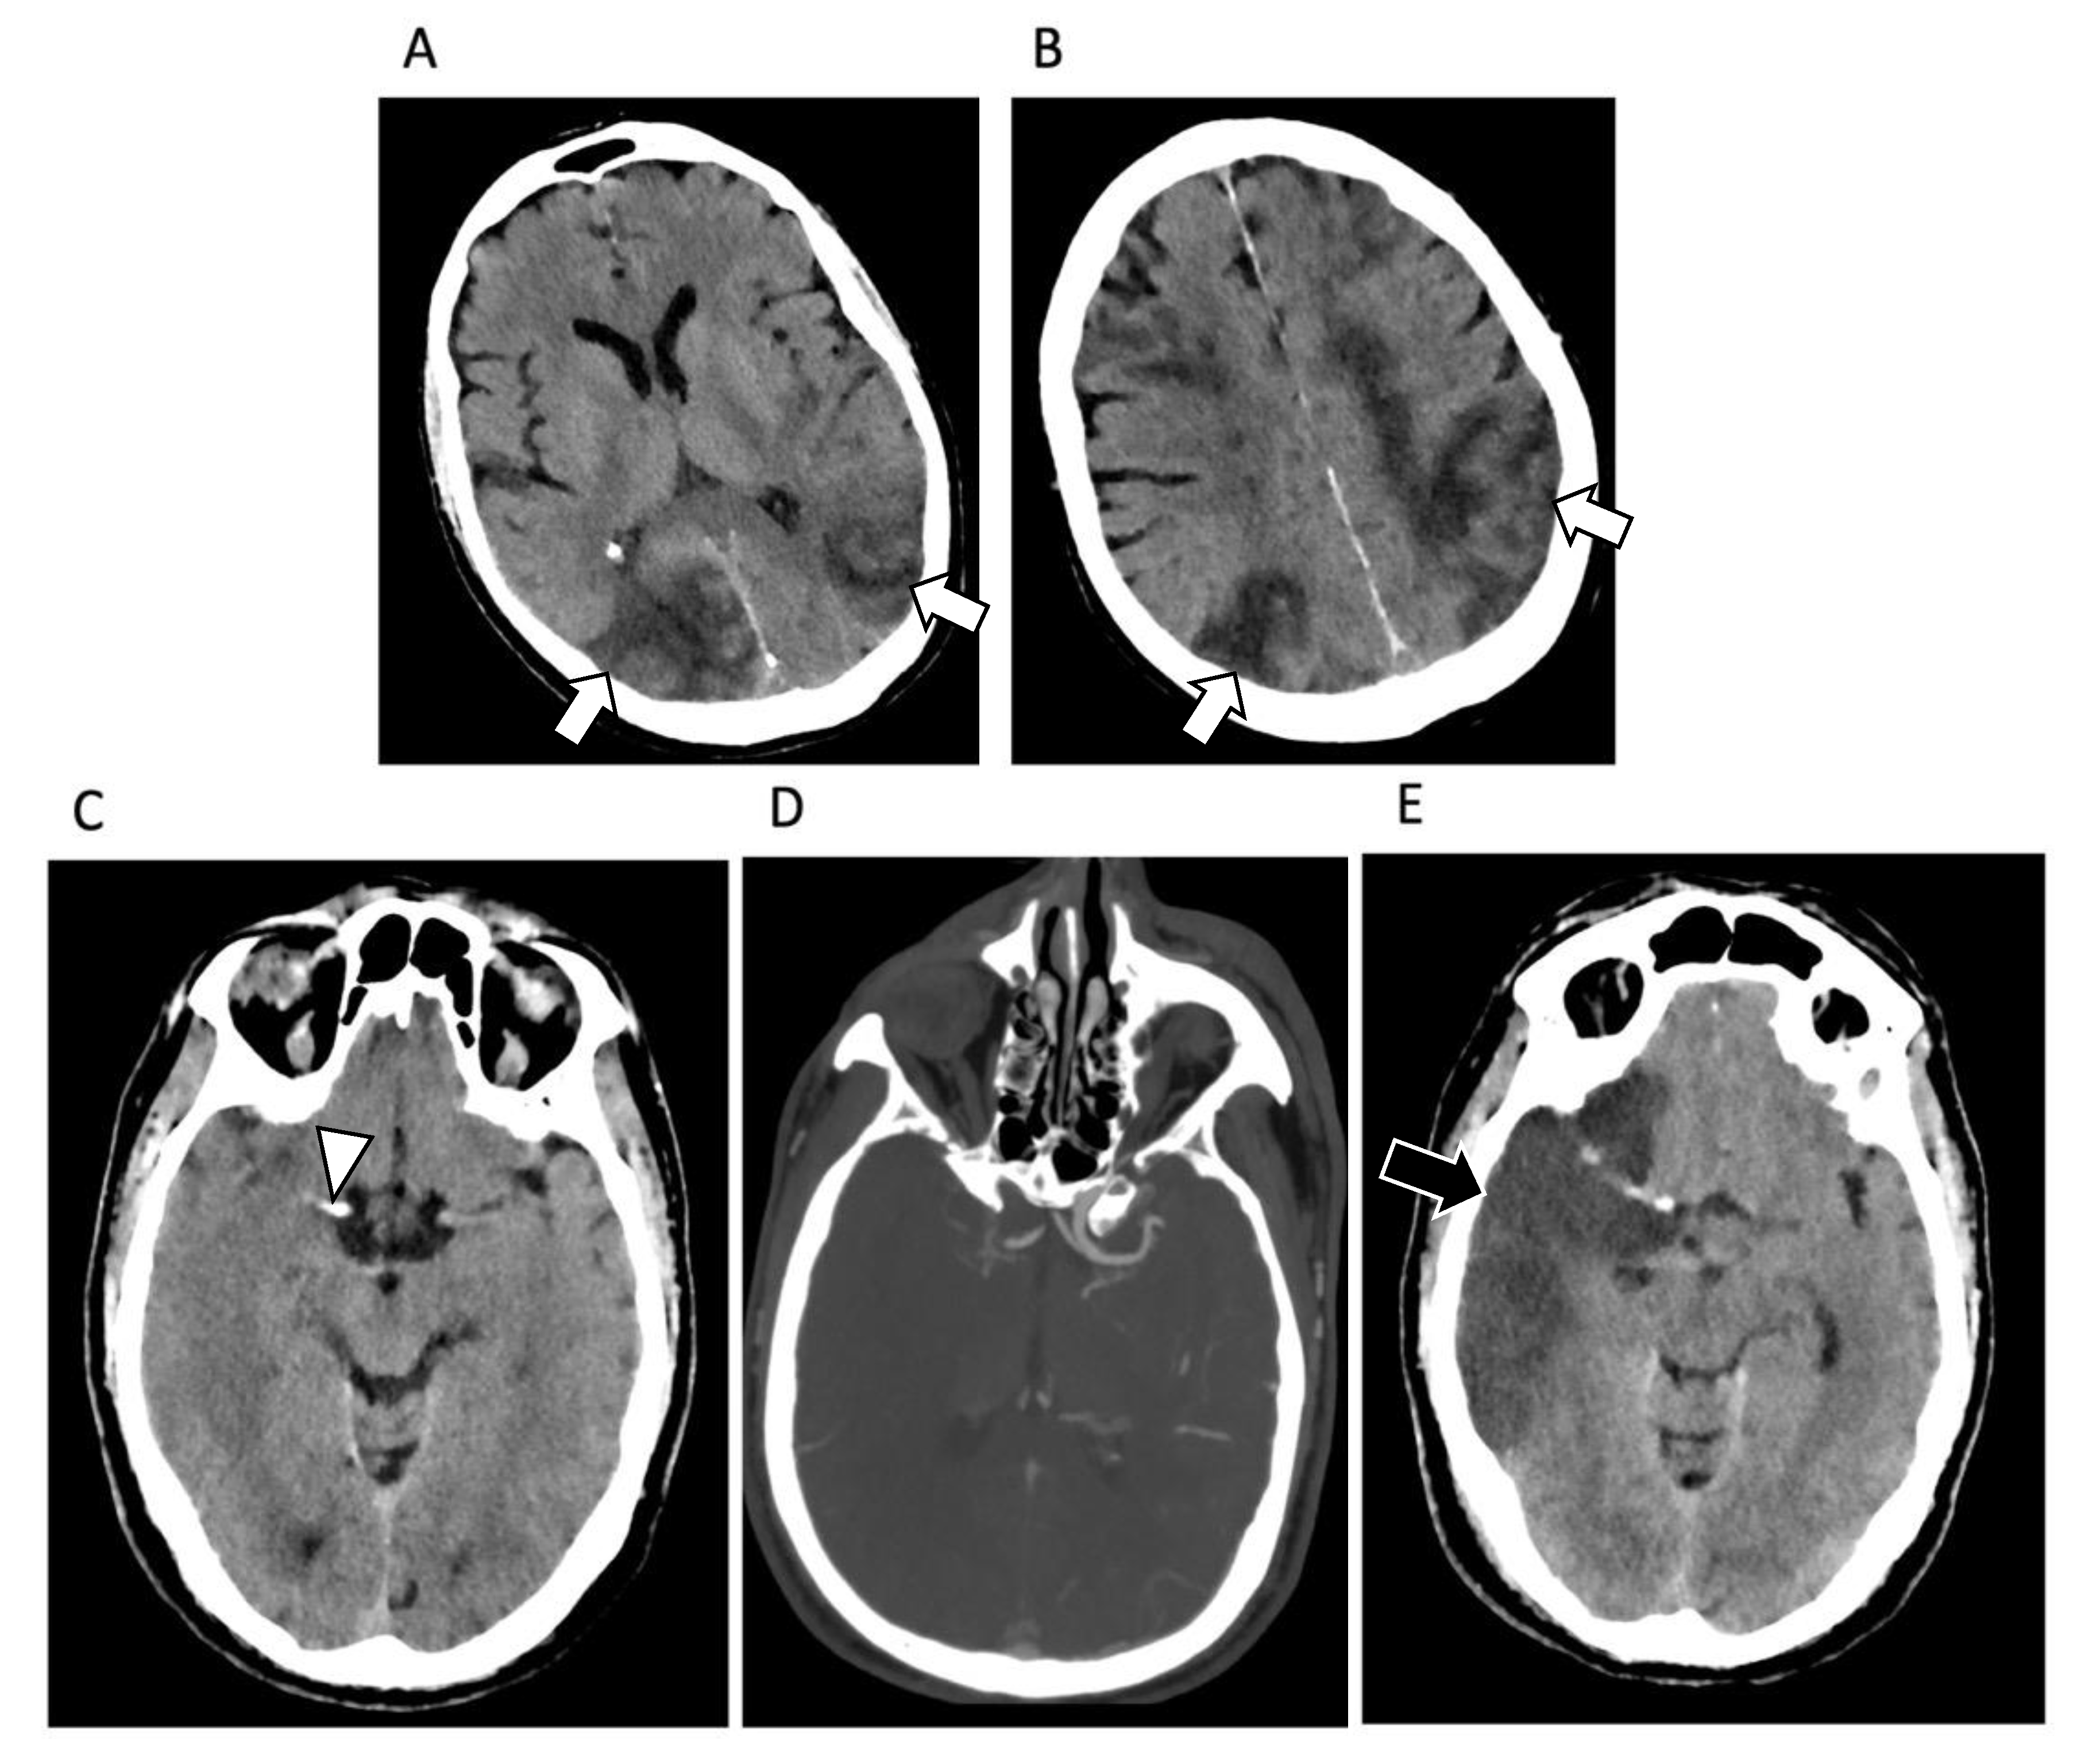

4. Central Nervous System Involvement